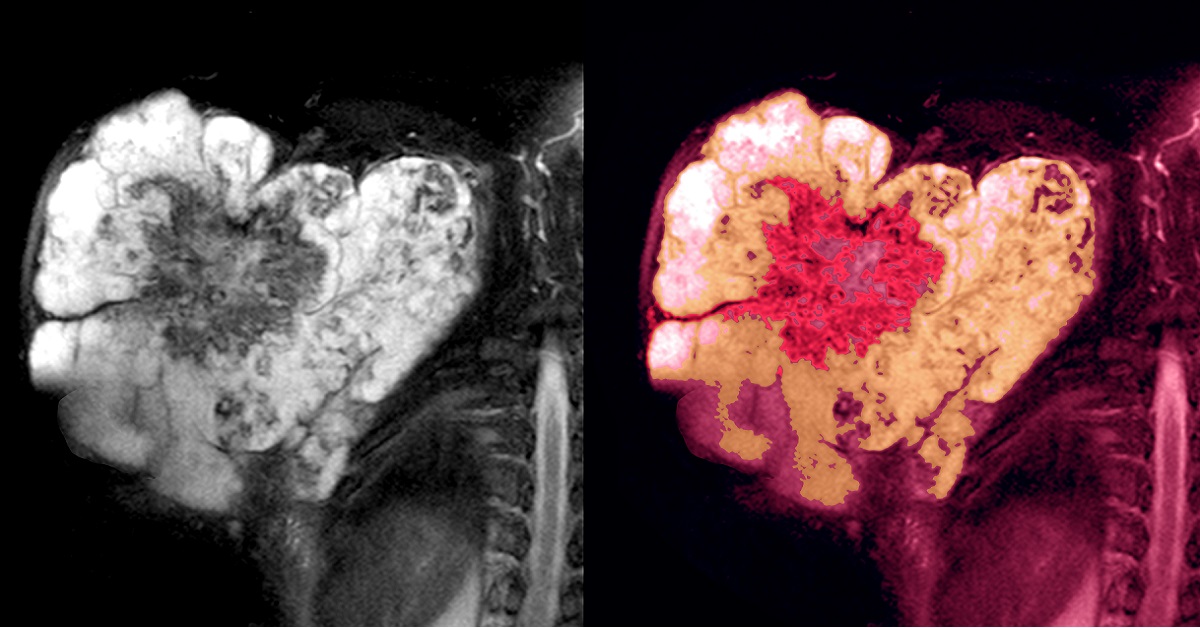

هو سرطان يحدث تحت الجلد ويكون في أعضاء الأنسجة الرخوة مثل: الطبقات الدهنية، العضلات، الأوعية الدموية، الأعصاب، وما إلى ذلك، حيث أنّ آلية التشخيص والعلاج تختلف من نسيج إلى آخر، باختلاف شكل النسيج الرخو في كلّ منطقة من مناطق الجسم.

كما أنه يصيب جميع الفئات العمرية، إلّا أنّ الإصابة به نادرة الحصول. فوفقاً للإحصاءات التي تمّ جمعها، تفيد أنه يمكن العثور على 3 مصابين فقط من بين 100 ألف شخص (أي بنسبة 0.003 في المئة).

أمّا في ما يخصّ أعراض مرض ساركوما الأنسجة الرخوة، فتكمن في ظهور كتل أو نتوءات في أجزاء مختلفة من الجسم، مثل الذراعين أو الساقين ومناطق أخرى في الجسم، إذ أنّ تلك النتوءات تزداد في الحجم يوماً بعد يوم ما قد يزيد من خطورة الحالة. وقد تكون مؤلمة في بعض الحالات، فإذا كانت هناك جروح أو تقرّحات، تصبح مزمنة ولا تلتئم بسهولة.

ومن أجل الحصول على أفضل النتائج العلاجية لمرض ساركوما الأنسجة الرخوة، ينبغي الإسراع في العلاج. لأنّه كلّما كان العلاج أبكر كلّما كانت فرصة الشفاء أكبر. لاسيّما أنّ التدخّل الجراحيّ في هذا المرض هو أساس العلاج، إلى جانب العلاج الإشعاعي أو الكيماوي بعد الجراحة والذي يكون بحسب المؤشرات الضرورية له، من أجل تقليل فرصة العودة للإصابة بالمرض مرّة أخرى.

وفي حال انتشار المرض في الجسم، فإنّ العلاج الجراحي يعتمد على حجم الأضرار الناجمة عن هذا الانتشار، ما إن كان في الإمكان استئصال الورم بشكل كامل أو لا.

وإن تعذّر استئصاله كليّاً فسوف يعتمد الطبيب على العلاج بالأدوية في المقام الأوّل، على أن يكون الدواء بحسب النوع المحدّد لمرض الأنسجة الرخوة.